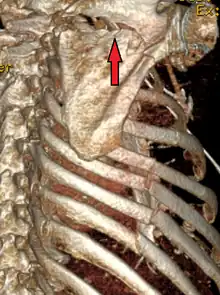

A right sided scapula fracture with rib fractures underneath seen on a 3D reconstruction of a CT scan